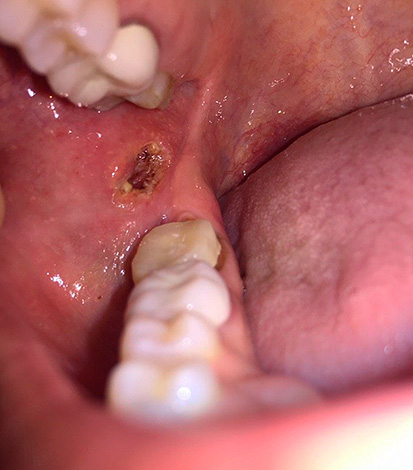

La foto sotto mostra il dente estratto con le cisti sulle radici: